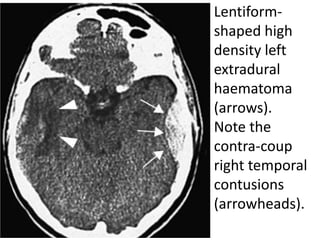

Lentiform-

shaped high

density left

extradural

haematoma

(arrows).

Note the

contra-coup

right temporal

contusions

(arrowheads).

Extradural haematoma

Characteristics EPIDURAL

● The majority of these are arterial (middle meningeal

artery) with a small proportion being of venous origin.

● Commonly unilateral and associated with a fracture in

adults. Skull fractures are often absent in children due to

skull elasticity.

● Haematoma forms between the inner table of skull and

the dura.

● May have associated injuries, such as a subdural

haematoma (SDH) or contusions.

● Arterial bleeding usually develops and presents rapidly

within 1 hour of injury whereas venous haematomas may

present after several days.

Radiological features

● CT signs include a biconvex hyperdense

elliptical collection with a sharply defined edge.

Mixed density suggests active bleeding.

● The haematoma does not cross suture lines.

● May separate the venous sinuses/falx from the

skull; this is the only type of haemorrhage to do

this.

● Mass effect depends on the size of the

haemorrhage and associated oedema.

● Venous bleeding is more variable in shape.

● Associated fracture line may be seen.